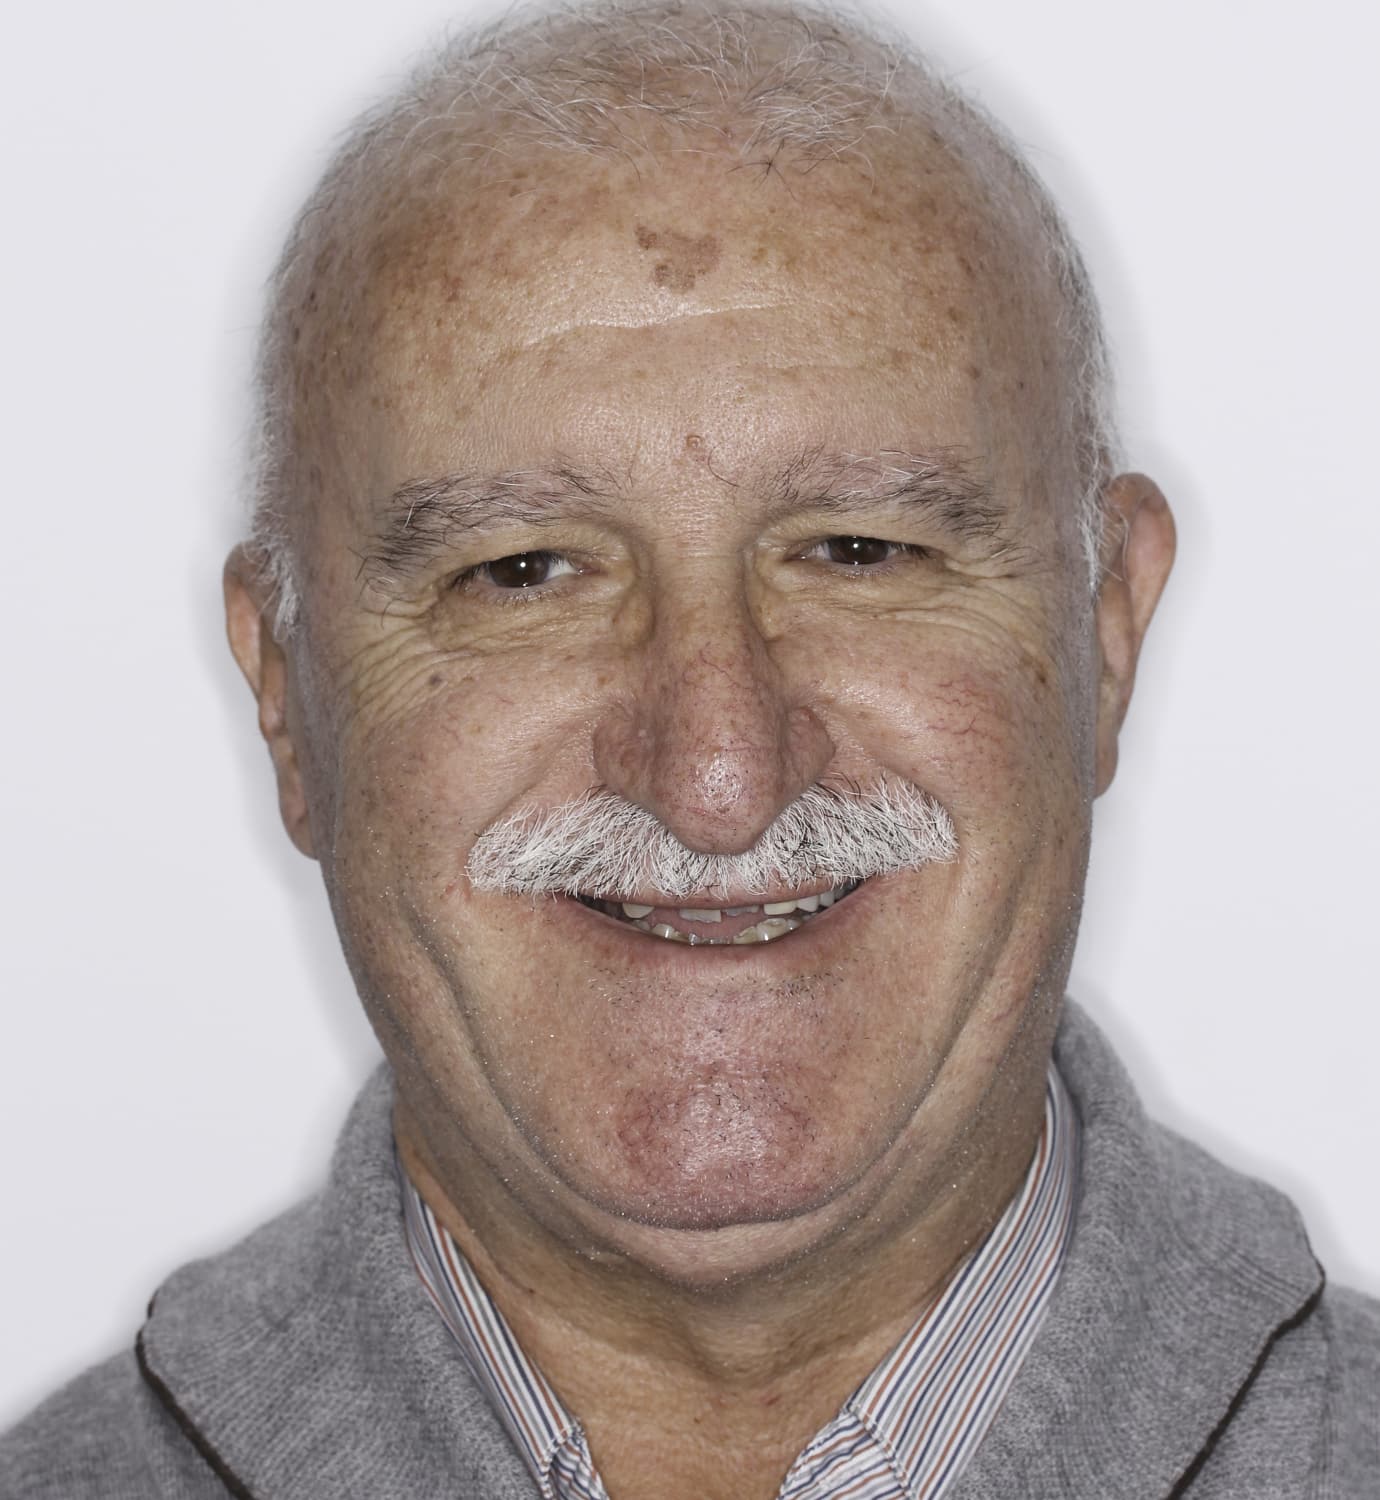

Jacinto vino a Ferrus & Bratos con una situación compleja: mostraba un número importante de ausencias dentarias, y las piezas dentales que permanecían en su boca presentaban fracturas, extensas lesiones cariosas y pérdida de soporte periodontal.

Analizando su caso, le propusimos una rehabilitación completa de la arcada superior con una prótesis híbrida sobre implantes. Con este plan de tratamiento queríamos alcanzar tres objetivos: mejorar su salud bucodental, facilitar el proceso de masticación y conseguir una oclusión perfecta y, por último, lograr un cambio significativo a nivel estético.